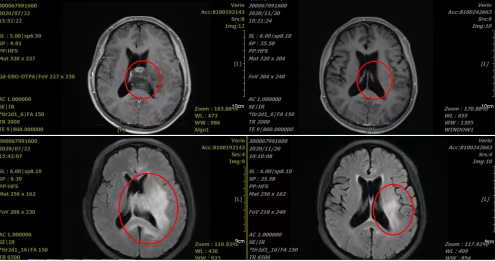

Case 2: The patient, female, 44 years old, sought medical attention due to "right lower limb weakness for over 2 years." A head MR showed diffuse abnormal signals in the bilateral lateral ventricles, corpus callosum, and left thalamus, suggesting glioma (Grade II-III). Diagnosis: Brain glioma. Carbon-ion radiotherapy began on July 28, 2020.

Treatment ended on August 24, 2020. The patient's limb muscle strength significantly increased, and no discomfort occurred during treatment. A review head MRI showed that the glioma in the bilateral lateral ventricles, corpus callosum, and left thalamus had significantly decreased in size compared to before treatment, and edema had reduced